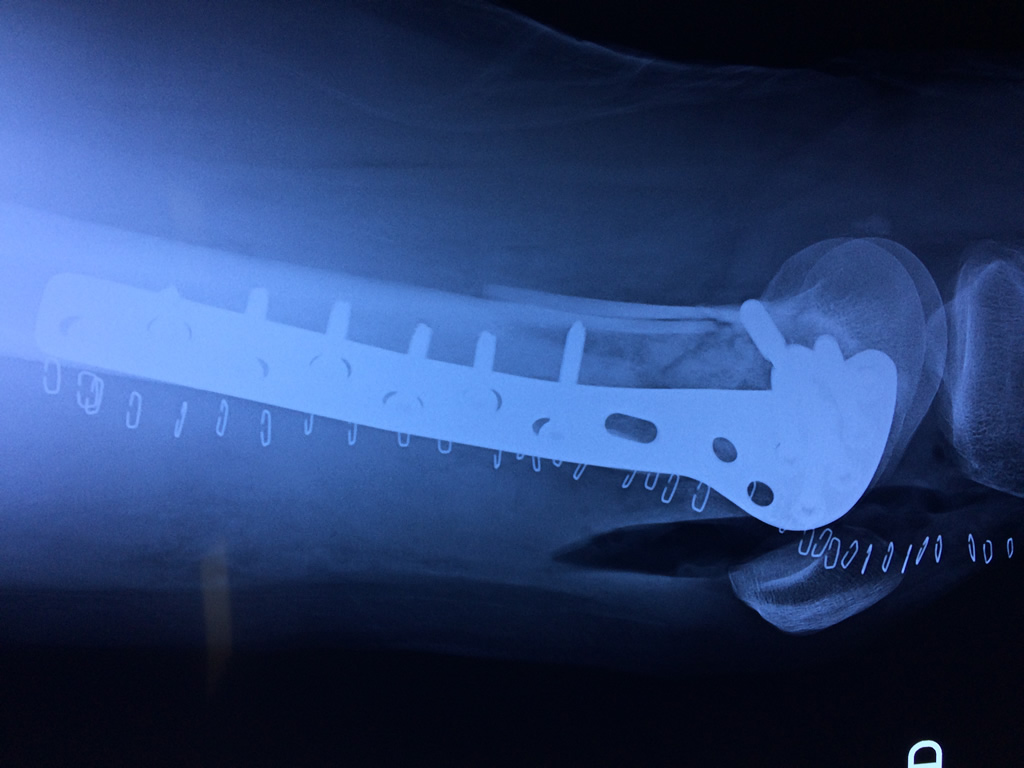

Cirugías de Hombros - Fémur

El fémur es el hueso del muslo, el segundo segmento del miembro inferior. Es el hueso más largo, fuerte y voluminoso del cuerpo humano.